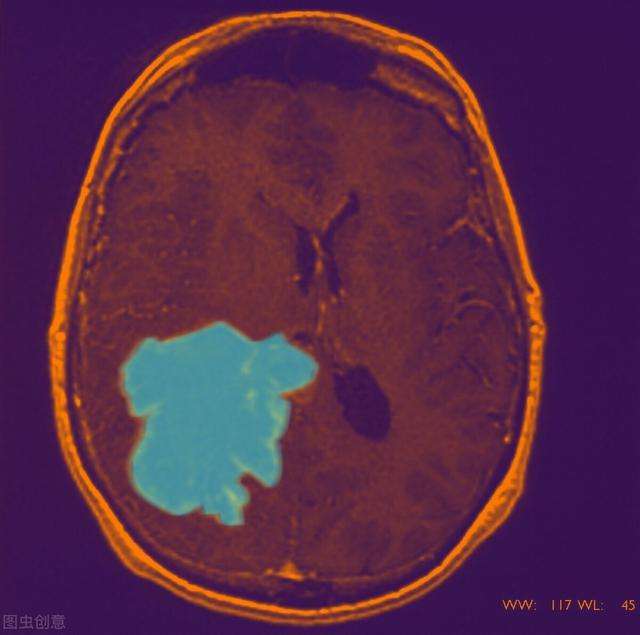

急性脑血管病脑出血发生的概率是非常高的 , 尤其是在秋冬季节交替的时间 , 体温自然下降 , 人体的血压有的人就会突然上升 , 很容易形成脑出血情况发生 。 脑出血在临床当中分为好多种 , 有高血压性脑出血 , 也有自身免疫性血管炎症或者淀粉样变性造成的脑出血 , 也可能是动脉瘤破裂而造成的脑出血 , 要完善相应的检查才能最终的明确 。 还一定要明确的就是脑出血在后期的治疗方案 , 就一定要明确头部CT , 头部CT可以查到脑出血的相关的量 , 周围的毗邻组织关系 , 再结合患者的整体状态进行相应的治疗方式 , 选择保守和外科手术都可以 。 但是明确具体的病情这样最重要 , 不同的手术方式也有不同的治疗效果 。 (三甲医院神经外科主治医生 , 擅长脑出血、脑梗死、脑挫裂伤、硬膜下血肿、硬膜外血肿、颅脑肿瘤、脑膜瘤、胶质瘤、听神经瘤、脑积水、颅内感染等脑部疾病 。 欢迎下方留言评论 。 )